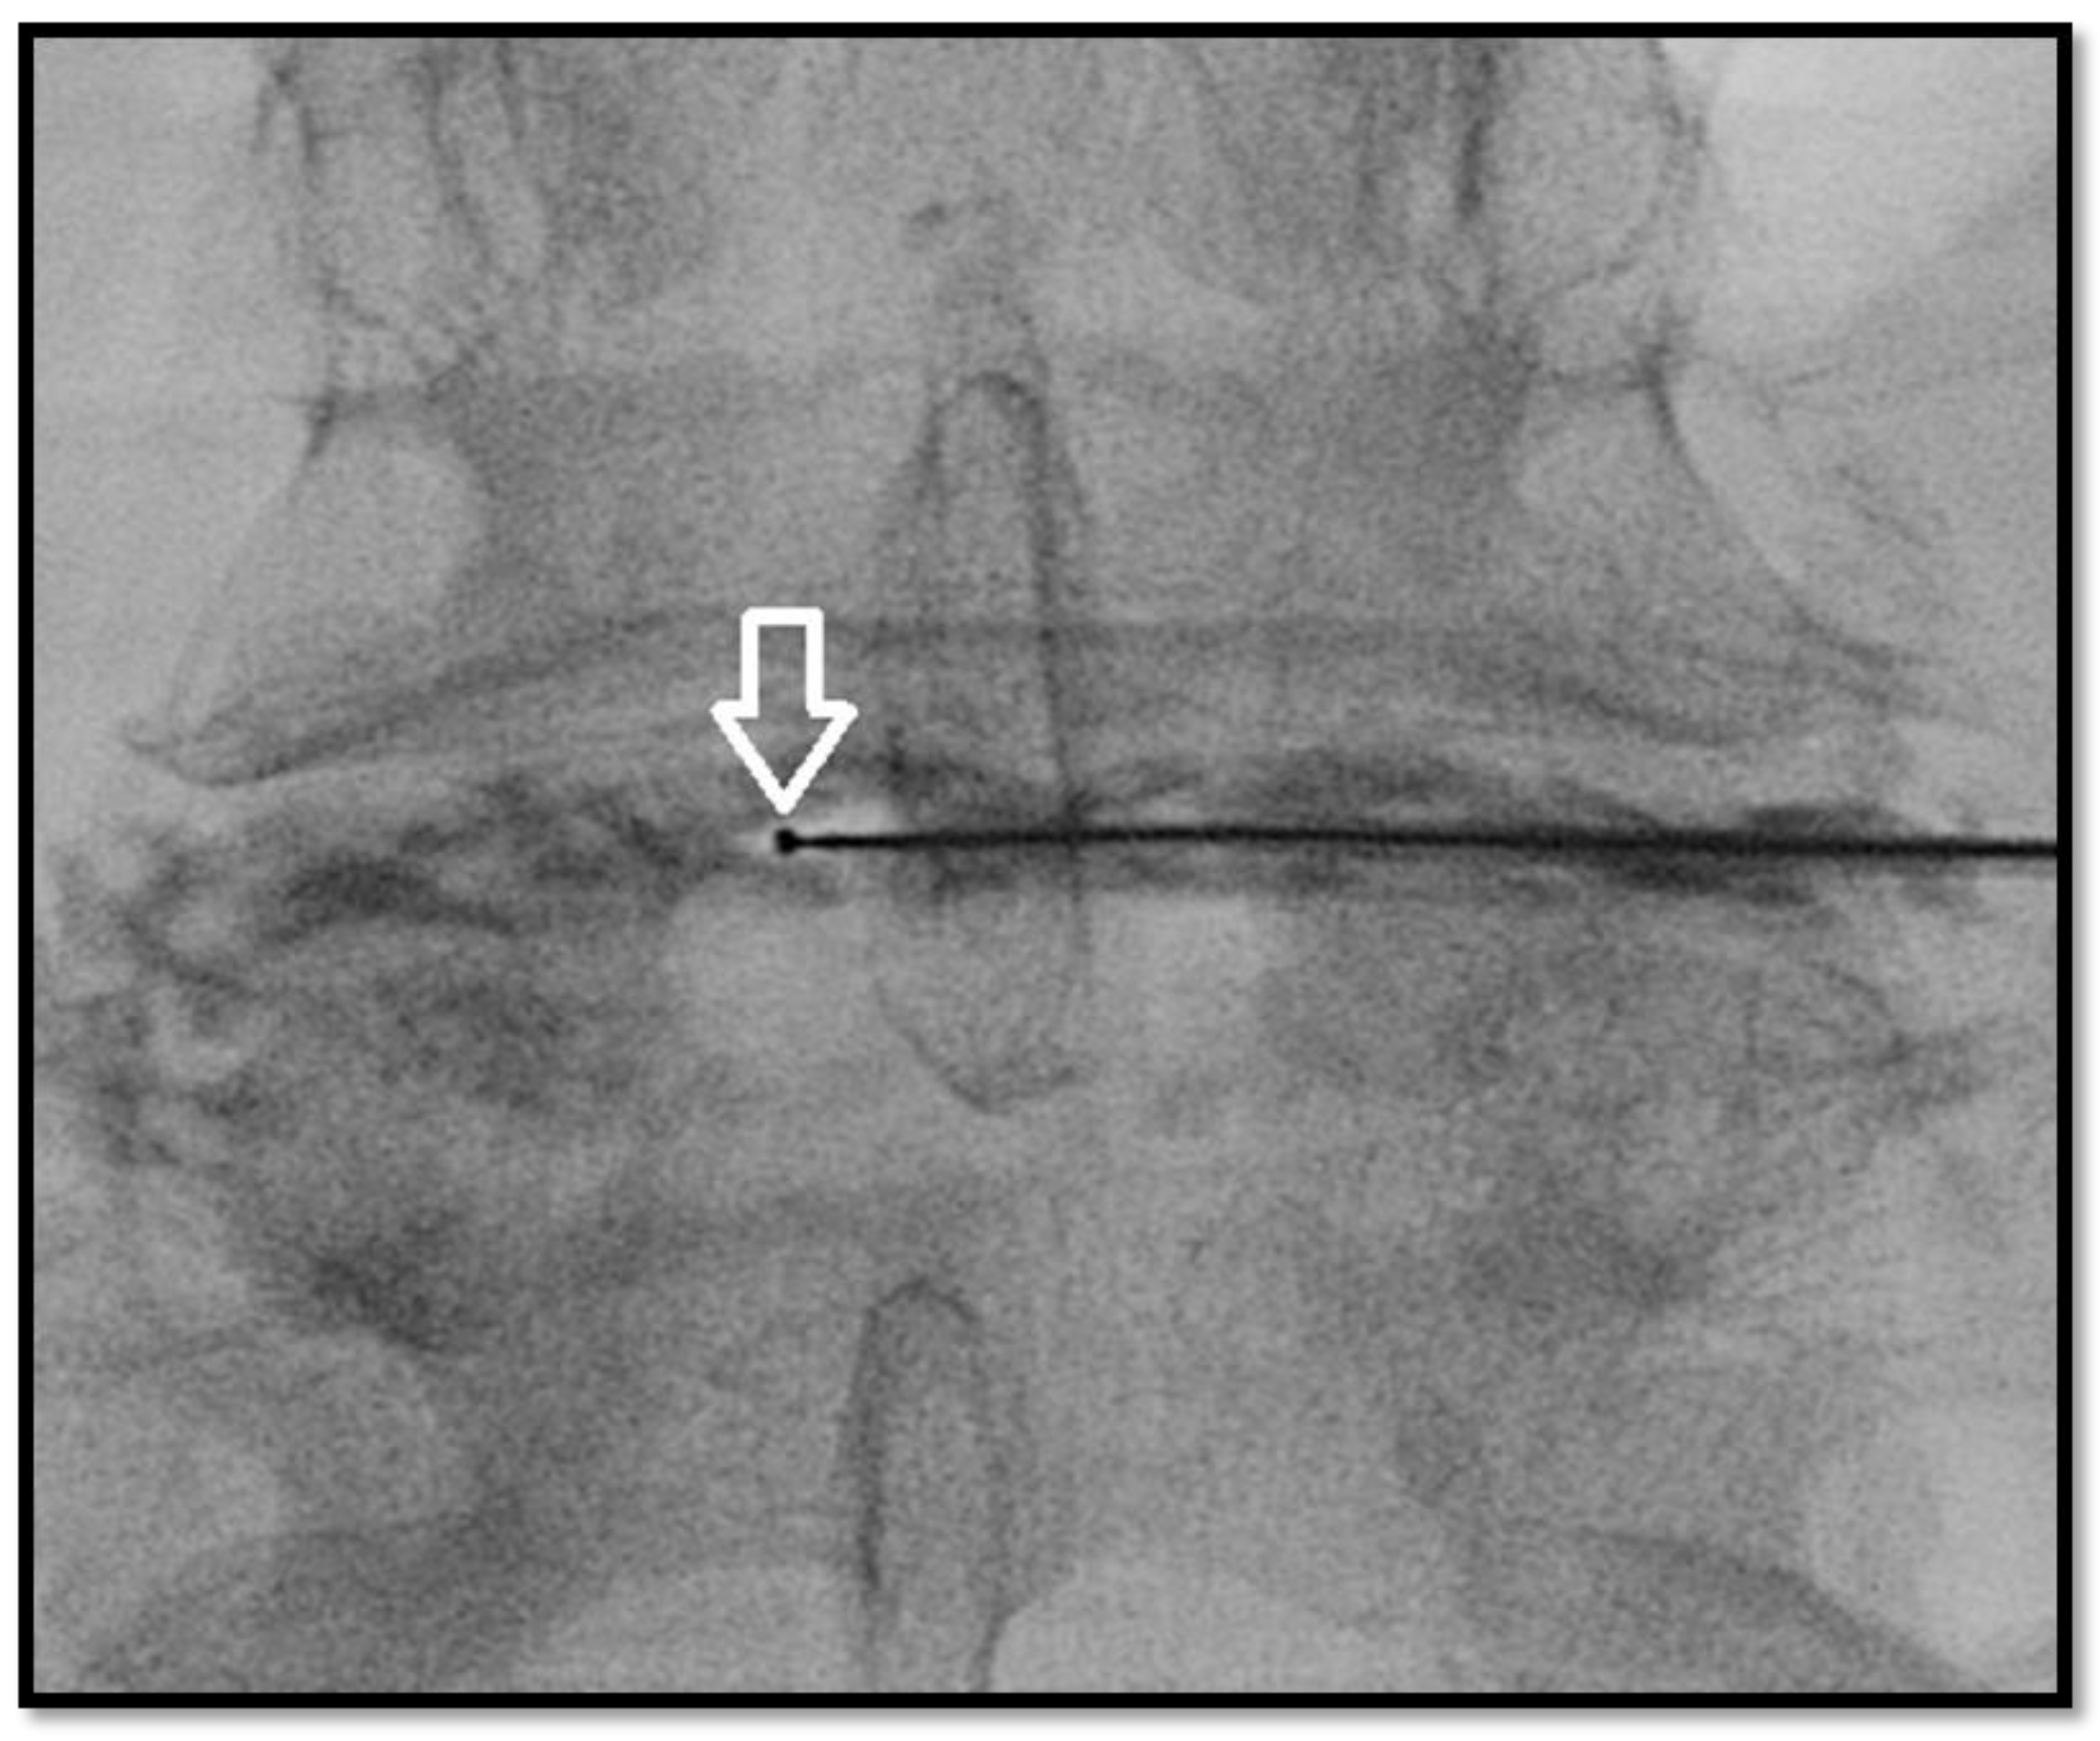

- Kelekis, A.; Filippiadis, D. Percutaneous treatment of cervical and lumbar herniated disc. Eur. J. Radiol. 2015, 84, 771–776. [Google Scholar] [CrossRef]

- Amoretti, N.; Huwart, L.; Marcy, P.Y.; Foti, P.; Hauger, O.; Boileau, P. CT-and fluoroscopy guided percutaneous discectomy for lumbar radiculopathy related to disc herniation: A comparative prospective study comparing lateral to medial herniated discs. Skelet. Radiol. 2013, 42, 49–53. [Google Scholar] [CrossRef]

- Ezeldin, M.; Leonardi, M.; Princiotta, C.; Dall’Olio, M.; Tharwat, M.; Zaki, M.; Abdel-Wanis, M.E.; Cirillo, L. Percutaneous ozone nucleolysis for lumbar disc herniation. Neuroradiology 2018, 60, 1231–1241. [Google Scholar] [CrossRef]

- Giurazza, F.; Guarnieri, G.; Murphy, K.J.; Muto, M. Intradiscal O2O3, rationale, injection technique, short- and long-term outcomes for the treatment of low back pain due to disc herniation. Can. Assoc. Radiol. J. 2017, 68, 171–177. [Google Scholar] [CrossRef]